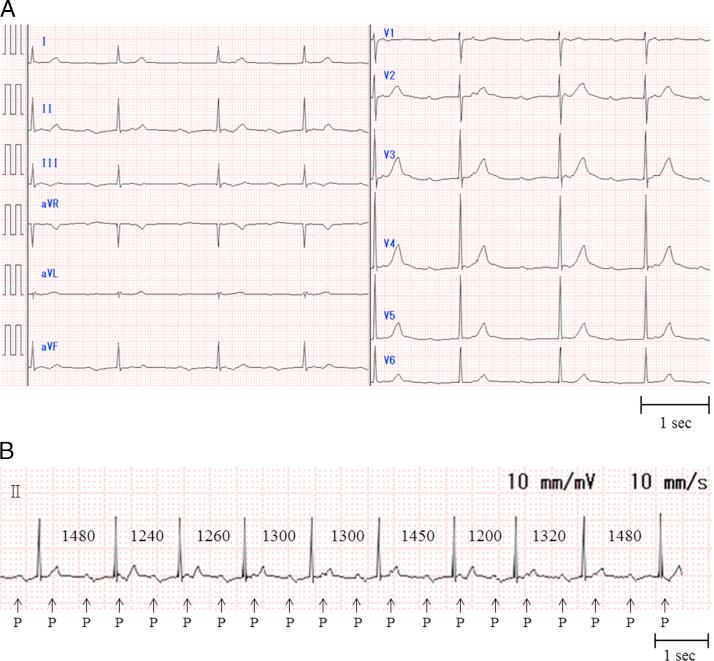

Tachycardia-induced cardiomyopathy long after a pacemaker implantation for the treatment of unusual 2:1 atrioventricular block: What is the mechanism?

HeartRhythm Case Rep. 2015 Oct 20;2(1):107-110. doi: 10.1016/j.hrcr.2015.09.009. eCollection 2016 Jan.